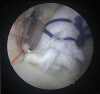

Capsulolabral augmentation is one of the most used arthroscopic techniques to address multidirectional instability of the shoulder. Given the thin and weak capsule seen in the affected patients, reconstruction in this subset of patients can be particularly challenging. This arthroscopic technique aims to reduce the capsular volume and deepen the glenoid socket through the creation of a particularly voluminous "bumper" along the glenoid bone. Increasing the depth of the glenoid facilitates a concavity-compression stabilizing effect and, therefore, shoulder stability, especially midrange stability. This technique aims to augment the bump of the standard capsulolabral reconstruction by using a resorbable surgical mesh derived from porcine skin.